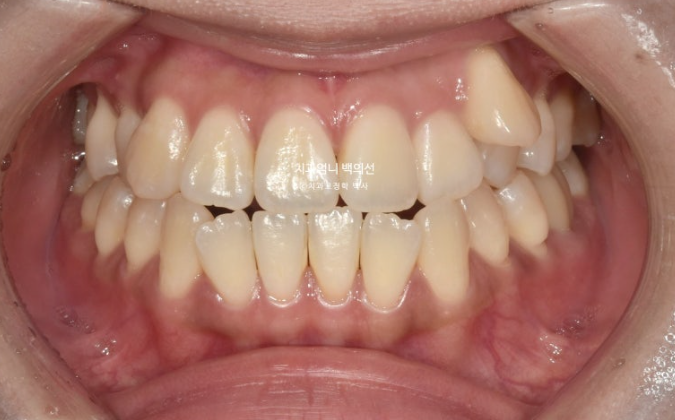

23년 8월, 교정치료를 위해 내원한 환자분입니다.

고치고 싶은 것은 단 하나 <덧니> 였습니다.

23.09

왼쪽 송곳니 하나가 완전히 배열에서 벗어나 있습니다.

덧니가 있으면 덧니쪽으로 중심선이 쏠리기 마련입니다.

위 앞니 중심선이 덧니쪽으로 틀어져 있는 것이 보입니다.

송곳니가 덧니가 제자리로 들어올 공간이 단 1mm도 없습니다.

심한 덧니입니다.

앞니는 윗니가 아랫니를 덮지 못하고 거꾸로 물리는 반대교합과 절단교합이 보입니다.

이 경우 입을 다물때 아랫입술이 나와보이고 입매가 부자연스럽습니다.